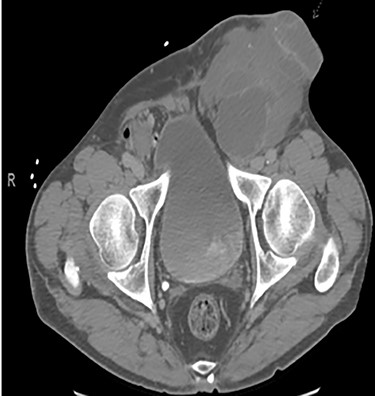

A 56-year-old male with a history of left testicular cancer treated with chemotherapy (Bleomycin, Etoposide, Cisplatin; BEP), radiotherapy, retroperitoneal lymph node dissection, and partial left nephrectomy in 1992 presented to hospital with complaints of left lower abdominal mass for 3–5 years, associated with ulceration and active drainage. He was asymptomatic with β-hCG and alpha-fetoprotein (AFP) levels within reference ranges (<2.39 and 1.4, respectively). On examination, inspection of abdomen revealed well-healed midline scar with bilateral incisional hernias and a 10 × 8 cm mass in the left lower quadrant (Fig. 1) firm and fixed to the abdominal wall. An open lesion characterized by yellow, non-purulent drainage was noted in the left lower quadrant. CT imaging of abdomen and pelvis with contrast revealed a multiloculated large cystic mass in the left inguinal canal measuring 11 × 7 × 7.7 cm (Fig. 2) along with a similar soft tissue nodule in the right inguinal area. A right retroperitoneal soft tissue mass in the mid abdomen was also identified, measuring 3.3 × 4.2 × 5.7 cm (Fig. 3). Changes of prior left nephrectomy and orchiectomy consistent with treatment of previous left-sided testicular cancer were also noted.

CT scan axial cut evidencing a right retroperitoneal mass measuring 3.3 × 4.2 × 5.7 cm.